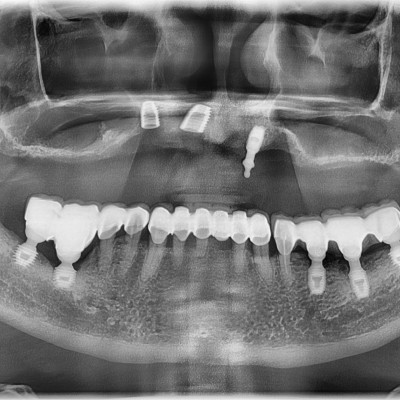

임플란트 재수술

임플란트 재수술 #12.13.22 타원 임플란트 제거 후 임플란트 수술+치조골 이식술 시행하였습니다.

임플란트 재수술 #44.45.46.47 타원 임플란트 보철물 제거 후 임플란트 재수술+치조골 이식술 시행하였습니다.

임플란트 재수술 #14.15.16.17 타원 임플란트 제거 후 임플란트 식립+ 치조골 이식술 시행하였습니다.